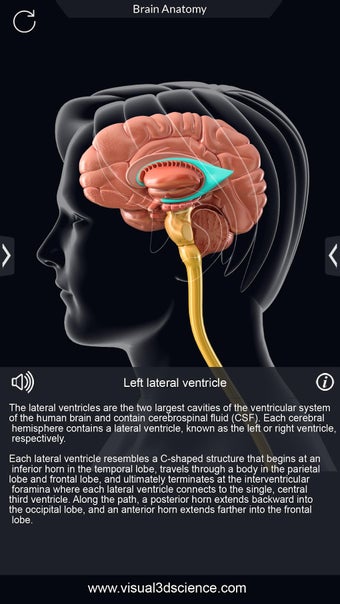

برنامج تشريح الدماغ Pro هو تطبيق تعليمي لدراسة تشريح الدماغ البشري. تم تصميم هذا التطبيق لكل من الطلاب الطبيين والجمهور العام. يتيح للمستخدمين استكشاف الدماغ من جميع الزوايا وعرض التشريح بطرق مختلفة. إنه أداة سهلة الاستخدام تتيح للمستخدمين تدوير 360 درجة والتكبير والتصغير وتحريك الكاميرا حول نموذج ثلاثي الأبعاد واقعي للغاية. يتيح للمستخدمين القدرة على تحديد الأجزاء وعرضها بالأشعة السينية وإخفائها وإظهارها وعرض الرسوم المتحركة في الوقت الحقيقي والرسم أو الكتابة على الشاشة ومشاركة لقطات الشاشة ونطق الصوت لجميع مصطلحات التشريح والمزيد. إنه تطبيق تعليمي مجاني.